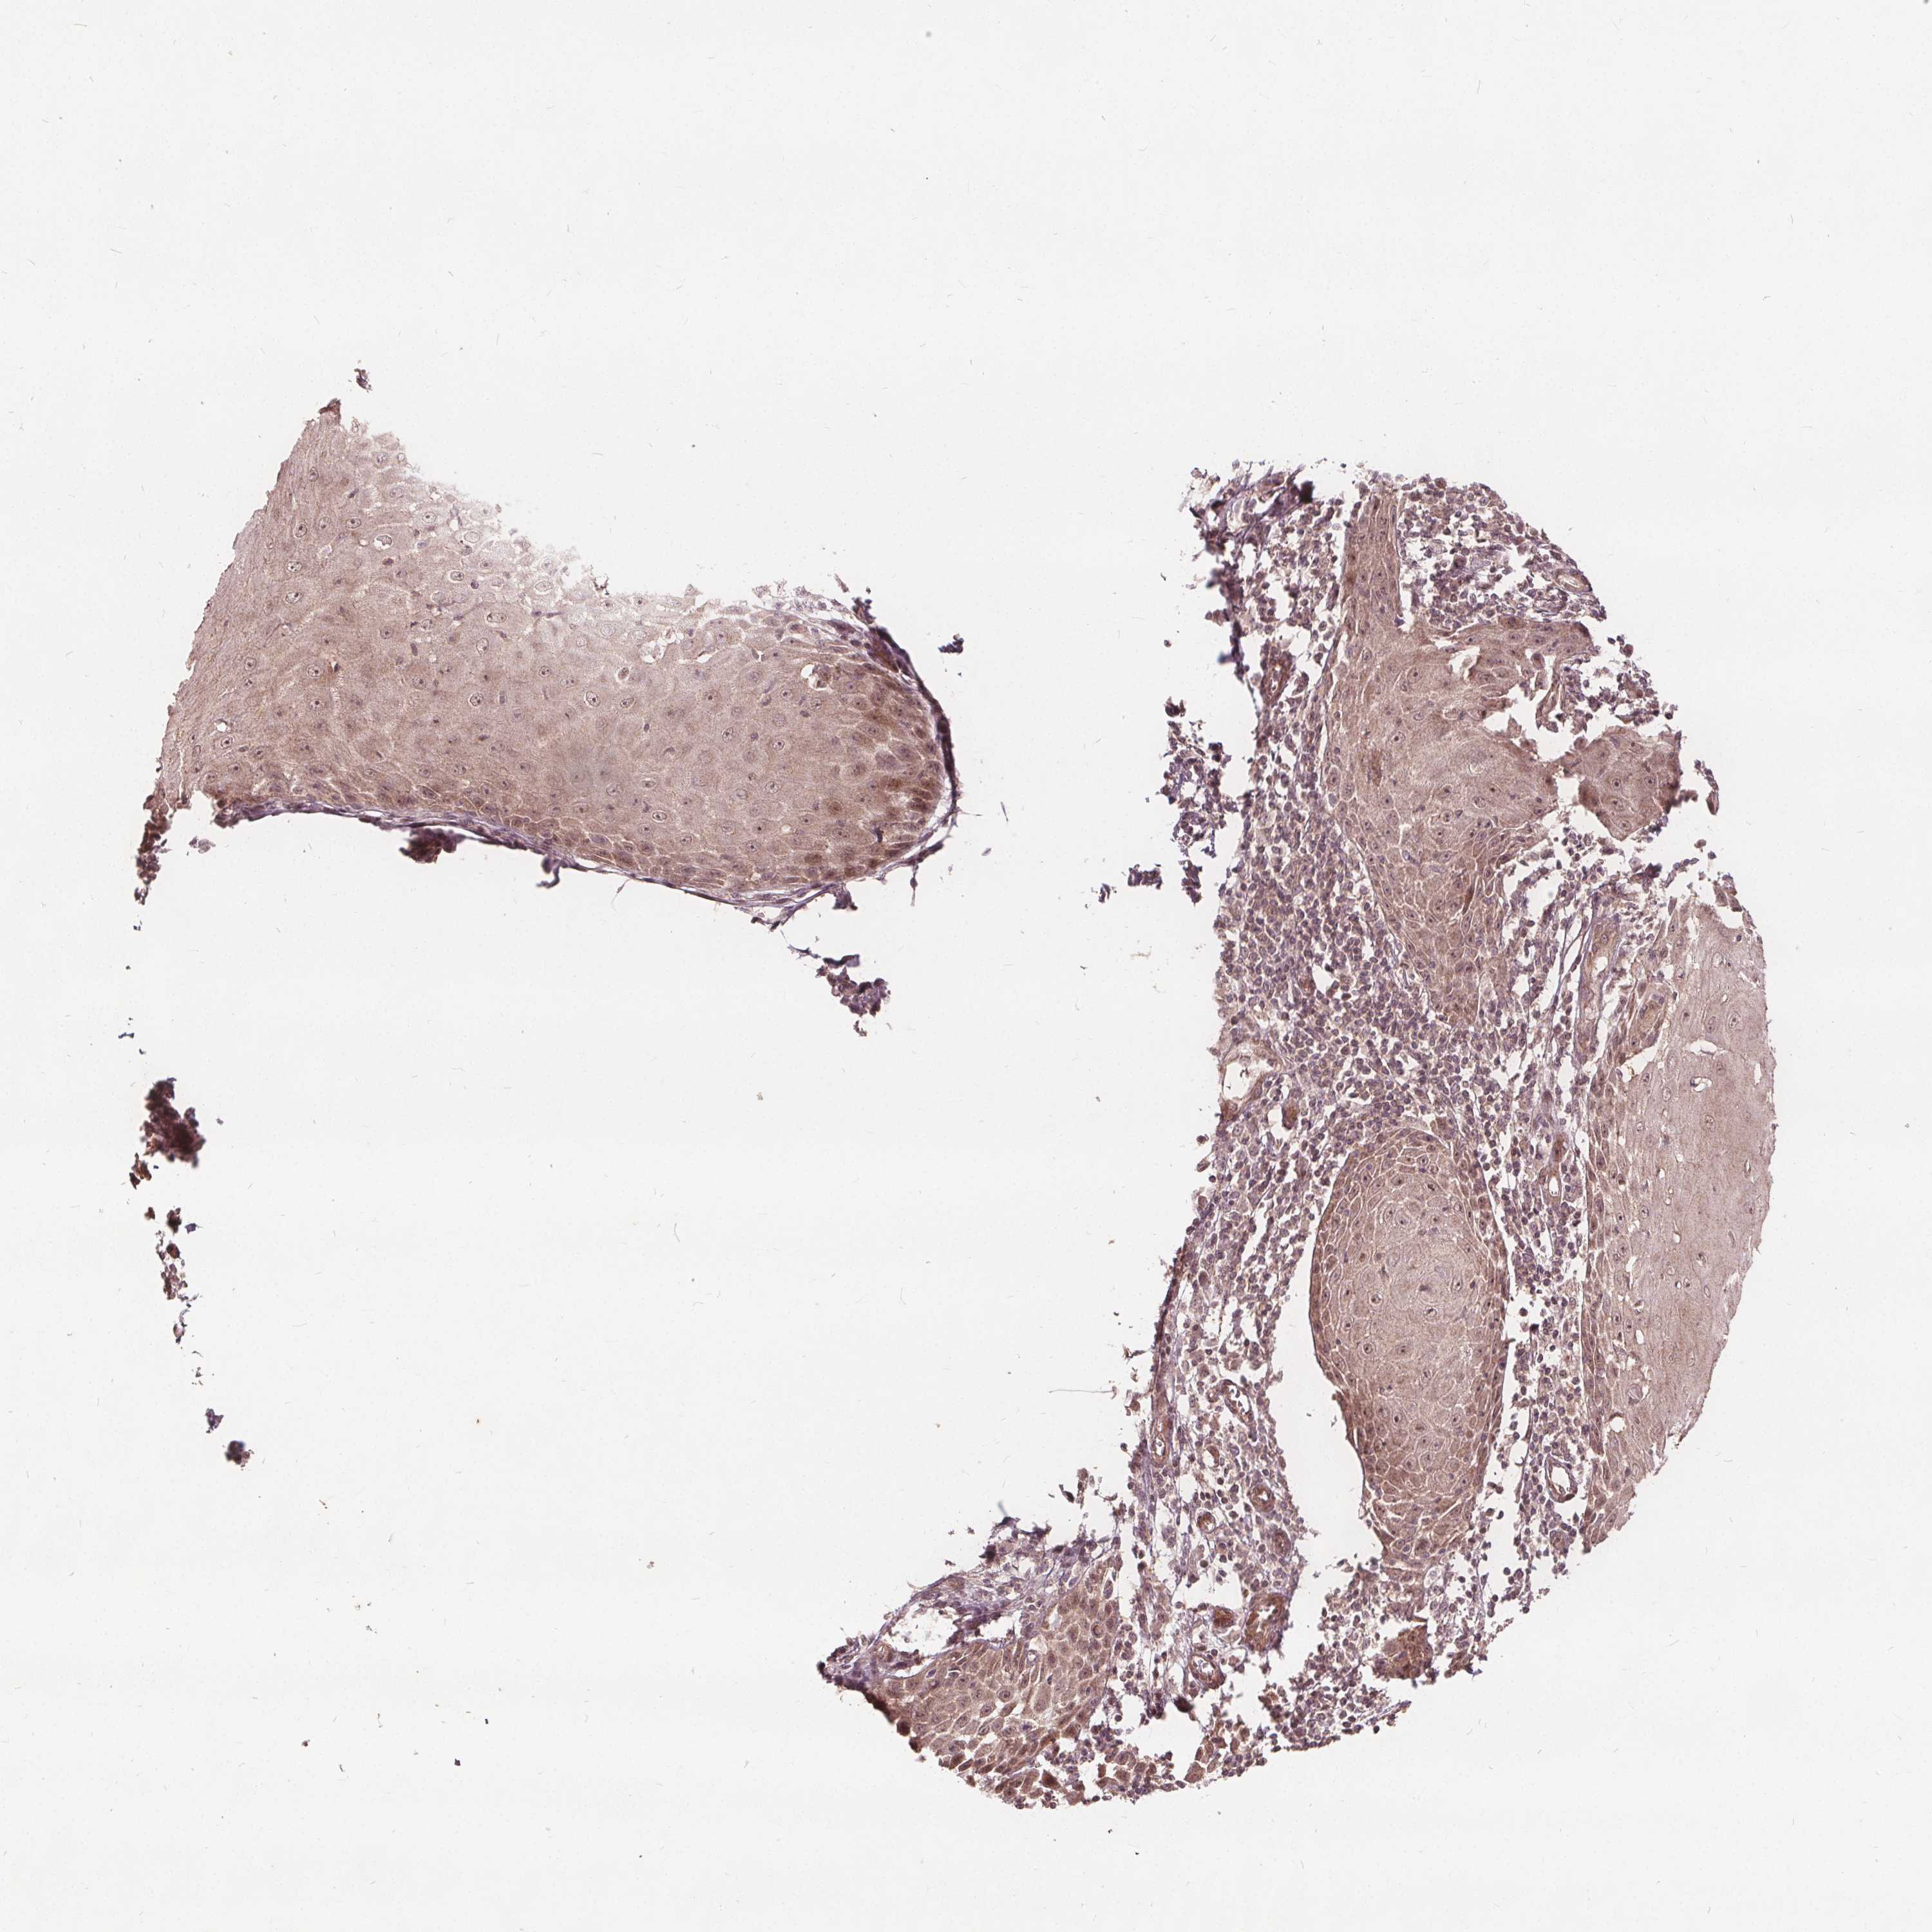

Basal cell and squamous cell cancer

SKIN CANCER - Protein expressioni

A mouse-over function shows sample information and annotation data. Click on an image to view it in a full screen mode. Samples can be filtered based on level of antibody staining by selecting one or several of the following categories: high, medium, low and not detected. The assay and annotation is described here.

Each image is clickable and will lead to virtual microscopy that enables deeper exploration of all samples and also displays staining intensity scores, fraction scores and subcellular localization as well as patient and tissue information for each sample.

Antibody HPA065425

Antibody CAB069426

Basal cell carcinoma

Squamous cell carcinoma, NOS

BCC, high aggressive